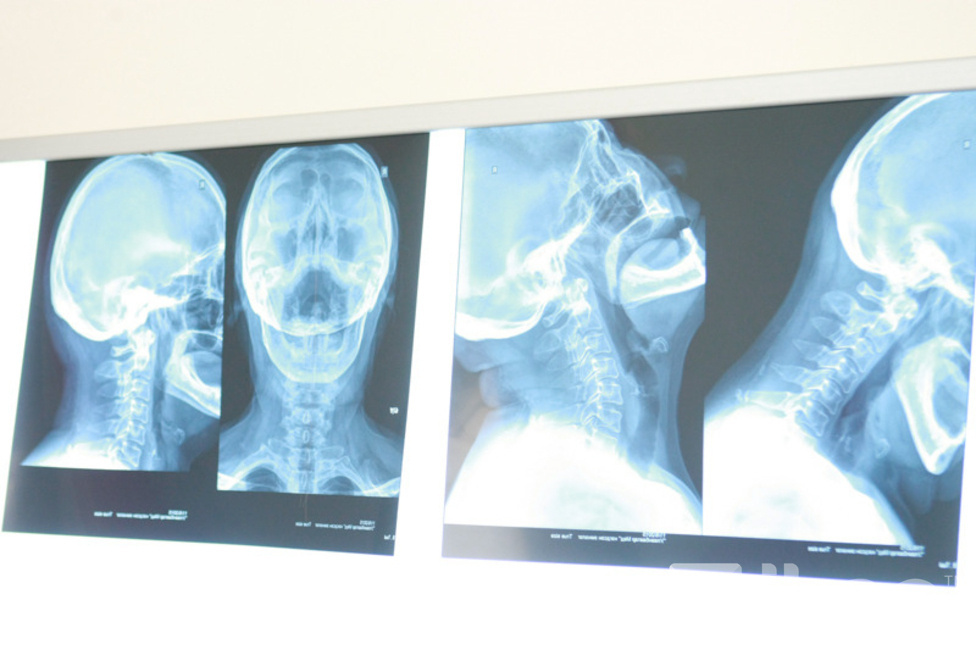

“Улаанбаатар Мед” нэгдсэн эмнэлгийн Мэдрэлийн их эмч Б.Зулчимэг “АНУ-ын Sigma компанид үйлдвэрлэгдсэн Yamasaki брэндийн Ультралайн аппарат нь мэдрэлийн эсийн түвшинд цахилгаан соронзон долгионоор үйлчилж, мэдрэлийн ёзоорыг сэргээх эмчилгээ хийдэг.

Эрүүл байхын гол үндэс нь хөл, гар, нүд, хүзүү бүгд тэгш хэмд байх. Ультралайн төхөөрөмж биеийг тэгш хэмтэй болгохын зэрэгцээ хуримтлагдсан өвчин, эмгэгийг мэсгүйгээр богино хугацаанд эмчилдэг. Өөрөөр хэлбэл цахилгаан соронзон давтамжаар мэдрэлийн эд, эсийг сэргээнэ.